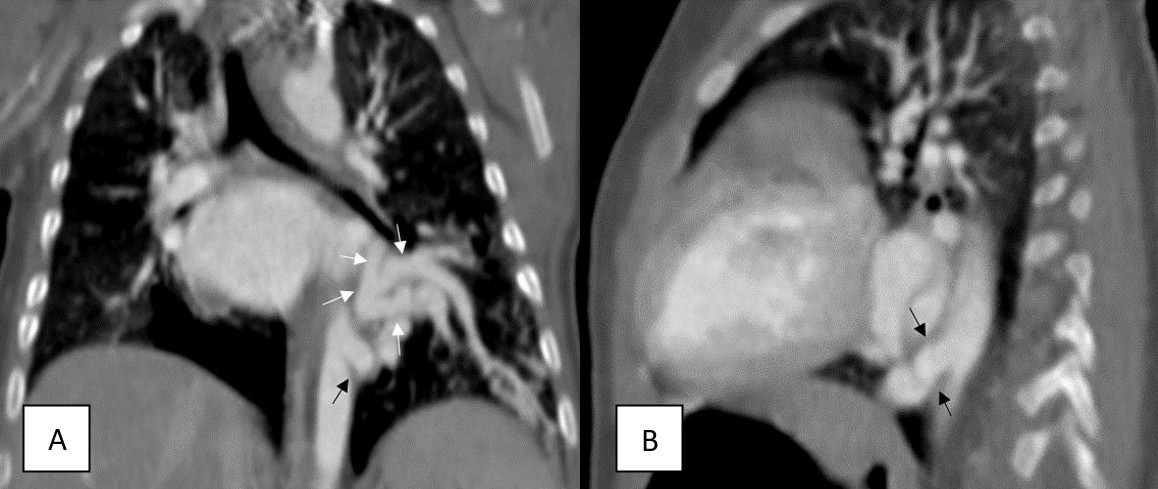

A 5-month-old infant was referred to our hospital after a suspected cardiac murmur was detected during a routine health check-up. Born via cesarean section at 39 weeks, the patient had no history of neonatal hospitalization, respiratory distress, or episodes of infection or bronchiolitis. Routine laboratory tests, including a complete blood count and assessments of kidney and liver function, were all normal. Chest X-ray revealed ground-glass opacities in the left upper and middle lung zones and opacification in the left lower zone (Figure 1). Thoracic CT and CT angiography were performed for further evaluation, with CT angiography demonstrating an aberrant vessel originating from the supradiaphragmatic descending aorta (Figure 2). This large systemic artery had three branches supplying the left lower lobe. Venous drainage from the affected lung parenchyma occurred via a dilated, tortuous left inferior pulmonary vein into the left atrium (Figure 3). No parenchymal abnormalities were observed, and the left lower lobe bronchus and its segmental branches appeared normal. These findings supported a diagnosis of pseudosequestration, as the affected lobe maintained a connection with the bronchial tree, differentiating it from true sequestration.